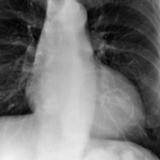

calcif Ao valve

Date: 01/26/2009

Views: 2909